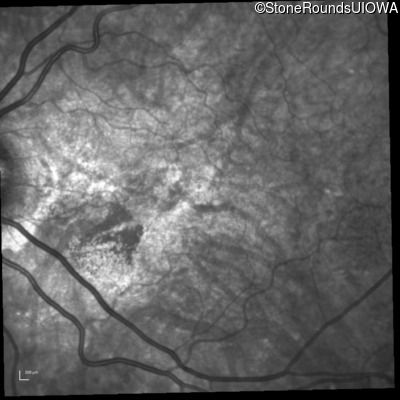

Infrared Fundus Photograph - Left - 20/30 -2 sc

Exemplar